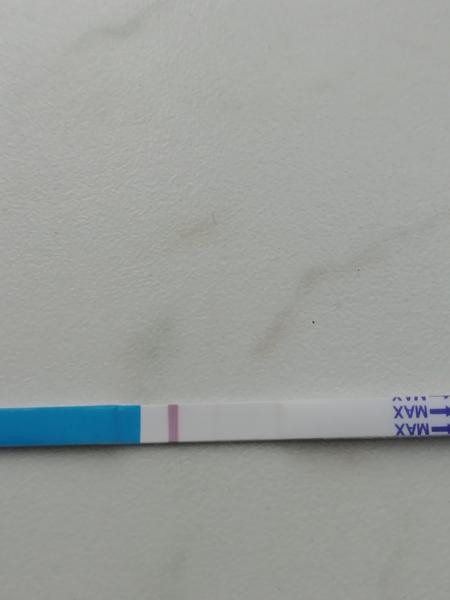

Test v den očekávané ms. Je to duch?

@rulexnone no krása gratuluji ♥ ♥ já dneska takto 😀 13 dnů od ovitrelle,12 dnů od IUI a 11DPO ♥ ve skutečnosti to už je reguální čárka ♥

@rulexnone asi taková jakou jsi měla včera ♥ ♥ ms mi nemá dojít za 3 nebo 4 dny ♥ ♥ ♥

@rulexnone Určitě bych testovala za 2 dny z ranní moči. Pokud bude sílit, je vše na dobré cestě 🙂 také jsem to tak měla a teď jsem 6+3